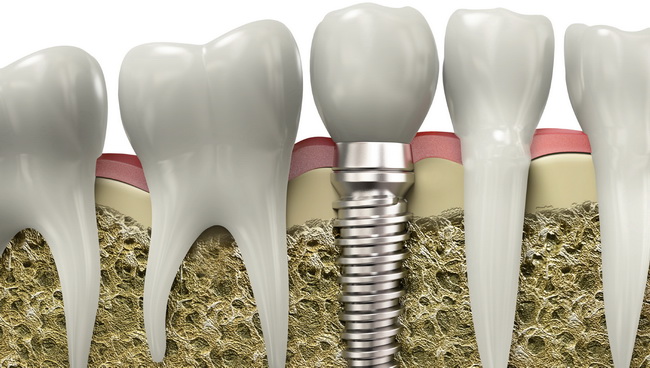

Zubni implanti ili implantati su cilindrični šrafovi koji se ugrađuju u kost vilice i koriste se kao zamena za prirodni koren zuba. Izrađuju se od titanijuma. Zajedno sa nadgradnjom i protetskom krunom zuba čine jedinstvenu celinu za funkcionalnu i estetsku rehabilitaciju jednog ili više zuba koji nedostaju. Kod same ugradnje implanta cilj je ostvariti kontakt spoljašnje površine implanta i okolnog koštanog tkiva kako bi srasli zajedno (pojava se naziva “osteointegracija“) i tako osigurali trajnost zubne nadoknade.

- Implantati se hirurški ugrađuju u kost. Postupak je brzo gotov i bezbolan, budući da se izvodi pod lokalnom anestezijom. Nakon ugradnje implant srasta sa kosti - “osteointegracija“ , što obično traje 2 do 6 meseci.

- Nakon ovog perioda na implant se postavlja nadgradnja (suprastruktura) na koju ide protetska krunica ili neko drugo protetsko resenje u zavisnosti od plana terapija.

- Manji gubitak koštanog tkiva - Biokompatibilni su i čuvaju kost oko sebe od propadanja. Implant čvrsto srasta sa viličnom kosti, čime se sprečava gubitak kosti i povlačenje desni, koji se često javljaju kod zubnih mostova i ispod proteza.